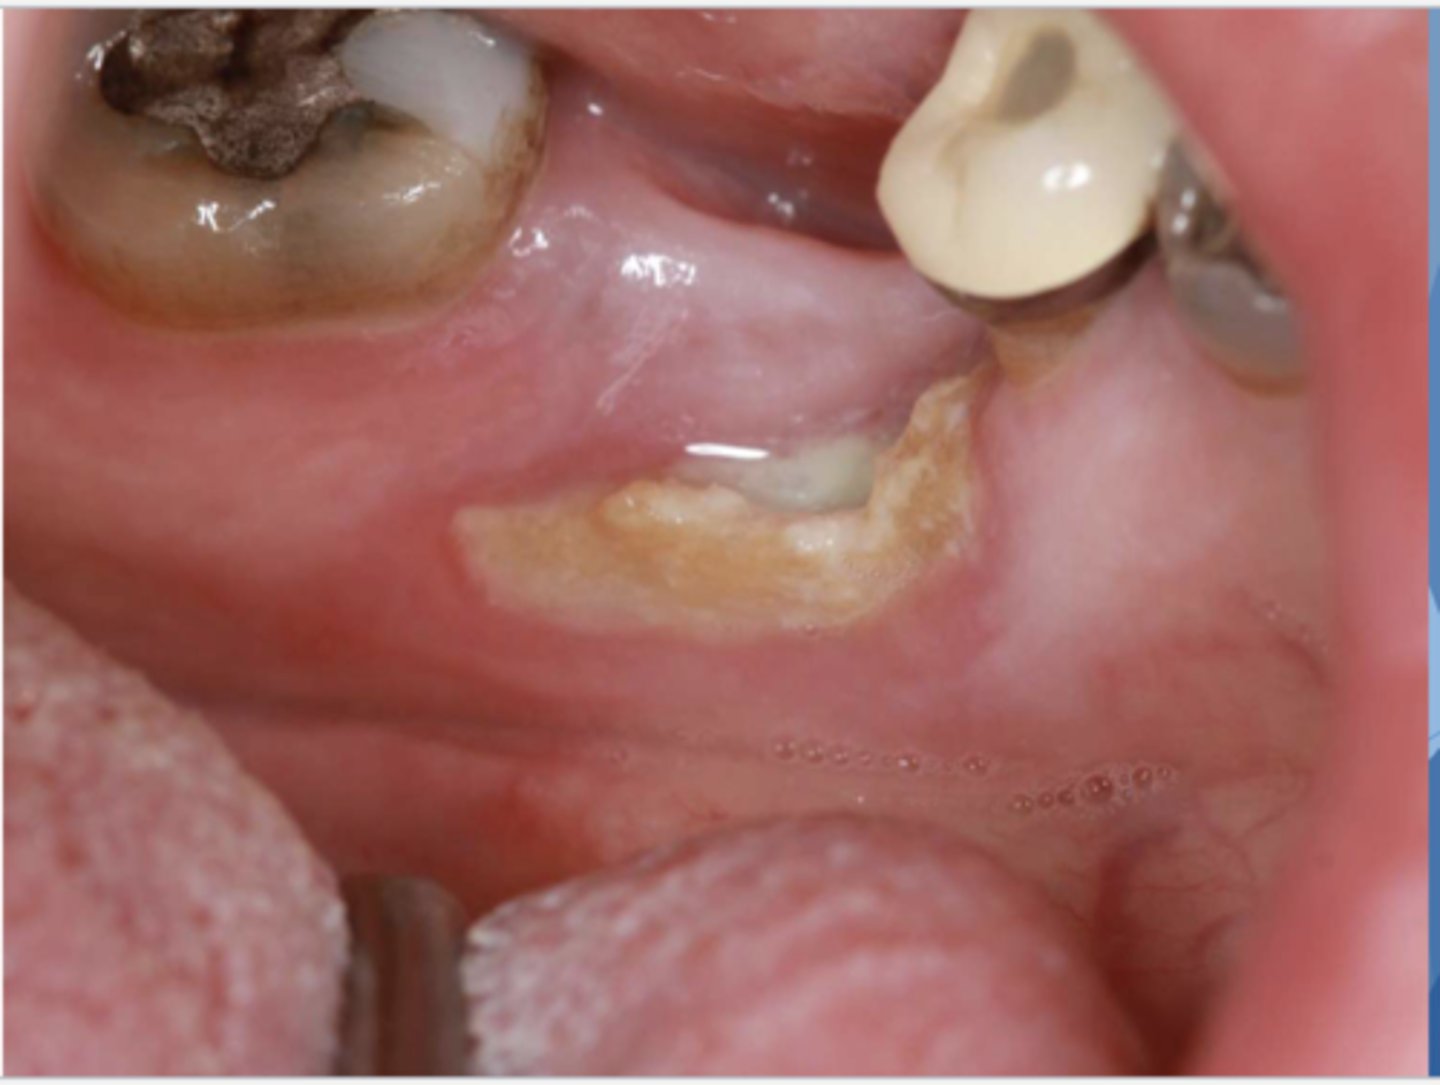

what do you suspect?

osteonecrosis

osteonecrosis/osteoradionecrosis/ MRONJ